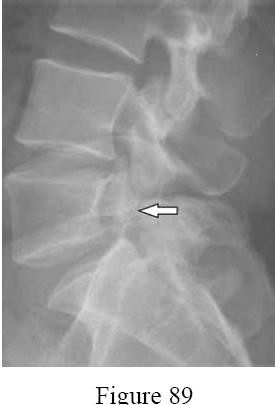

A 60-year-old male of East Asian descent presents with progressive clumsiness in his hands and an unsteady gait.

Lateral cervical radiographs reveal a continuous, dense radiopaque stripe immediately posterior to the vertebral bodies from C3 to C6. What is the most likely diagnosis?

Explanation